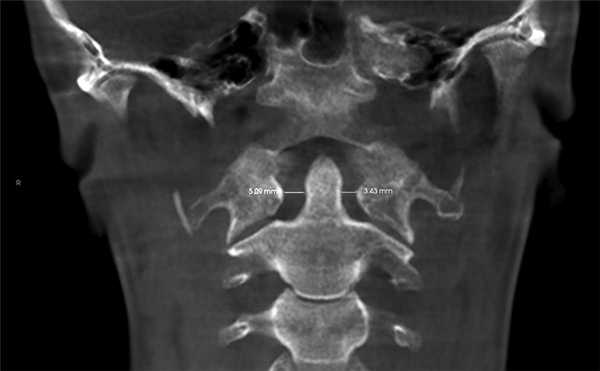

4. Краниовертебральное центральное соотношение по M. Rocabado. На КЛКТ также есть возможность анализа ротаций первого и второго шейных позвонков. Измерение проводят от заднего бугорка первого шейного позвонка к зубу второго шейного позвонка, при этом большее расстояние свидетельствует о ротации CI в данную сторону (рис. 9).

Рис. 9. Ротация первого шейного позвонка (CI) вправо, так как расстояние между CI и зубом CII больше с правой стороны — 5,09 мм; слева — 3,43 мм.

Ротации шейных позвонков, уменьшение функциональных пространств служат причиной головных болей напряжения и лицевых болей, поэтому при обнаружении данных патологий необходим комплексный подход в лечении.